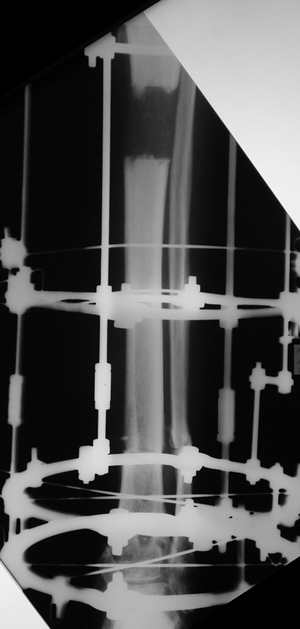

остеотомия м\б кости, аппарат Илизарова. По рентгенограммам в двух проекциях произведено планирование устранения смещений (рис 2 и 3), между вторым и третьим кольцом установлены 6 телескопических дистракторов Гесапода, данные введены в программу, и далее втечение 10 дней больная подкручивала телескопы согласно выданной компьютером инструкции. По завершению репозиции гексаподные телескопы обратно заменены на обычные штанги от аппарата Илизарова (рис 4 и 5). Еще через две недели забит гвоздь (рис 6, контроль

через 4 месяца).

Мужчина, 33 года, резекция б\б кости по поводу остеомиелита после открытого перелома. Стандартная методика билокального остеосинтеза (рис 1 и 2). В конце удлинения выявилось неудовлетворительное взиморасположение перемещенного фрагмента и дистального отломка (рис 3). Планирование (рис 4).

Адаптация отломков гексаподом за 5 дней (рис 5). Замена гексапода на обычные штанги (рис 6 и 7)